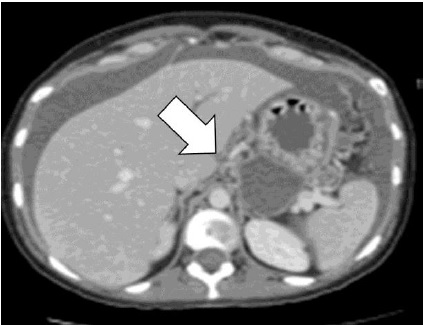

Durante el segundo día de hospitalización la paciente refiere mialgias, epigastralgias, lumbalgia y anorexia, solicitándose ultrasonido abdominal que demuestra engrosamiento de la pared gástrica con tumor de 5 x 4 centímetros y presencia de ascitis. Los valores de antígeno carcinoembriogénico (188 ng/mL, valor normal 0 – 3 ng/mL) y CA19-9 (1.791 U/mL; valor normal 0 – 37 U/mL) estaban elevados. La ecografía fetal y las pruebas de bienestar fetal estaban normales. El peso fetal estimado era de 1700 gramos. Se realizó gastroscopia que reveló linitis plástica y úlcera con bordes rugosos e hipertróficos en antro- cardias. La tomografía abdominal confirmó la tumoración gástrica que infiltra la muscular propia y la sub-serosa con compromiso de por lo menos 15 ganglios linfáticos de los tres niveles, sin metástasis observables (estadificación IIIC) y con ascitis importante (figura 1).